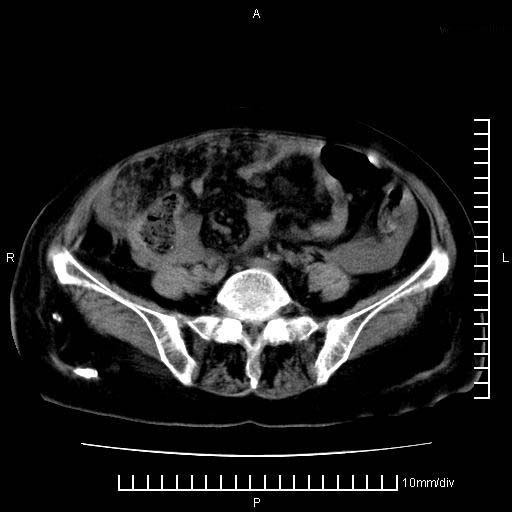

标题: CT28280:腹部增强:女性,80岁

上腹疼痛月余,外院核磁诊断胰腺癌。现临床示右下腹可明显触及包块,可片子上怎么没有看到?

胰腺体部癌累及周围器官,腹膜、粘连,临床摸到的可能是粘的组织

1、考虑胰腺癌伴腹膜腔转移,胸腹水。

2、肝脏转移可能。

3、右肾盂囊肿。

1)考虑胰腺癌并胰腺假性囊肿形成。2)肝内低密度灶,不排除转移。3)右肾盂积水。4)腹水。5)右侧胸腔积液并右肺下叶部分膨胀不全。

考虑胰腺ca伴腹膜腔转移、肝左叶转移、右肾积水。右胸腔积液。